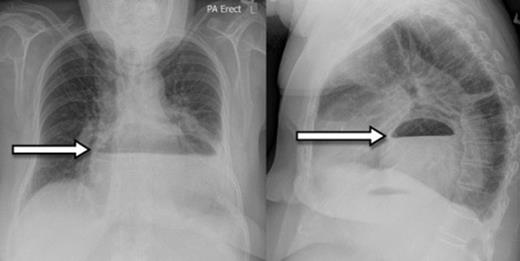

A 73-year-old Caucasian woman presented to the emergency department with 2-day history of vomiting and vague abdominal pain. Her background history included asymptomatic hiatus hernia, morbid obesity (BMI of 35.7), polymyalgia rheumatica, previous laparoscopic cholecystectomy, hypercholesterolaemia and hypertension. Regular medications included prednisone, amlodipine and cilazapril. On presentation she was tachycardic at 110 beats/min with otherwise normal vital signs. Her abdomen was generally tender but without any localised peritonism. Initial laboratory investigations on admission showed a leukocytosis (WCC of 13.8 x 109/L). Routine X-ray (figure 1) and subsequent (CT) scan (figure 2) both revealed a large strangulated paraoesophageal hernia. Radiographic changes (figure 3) were seen with gas within stomach wall, suggestive of gastric necrosis.

CT showing a large strangulated paraoesophageal hernia (arrow) within the thoracic cavity